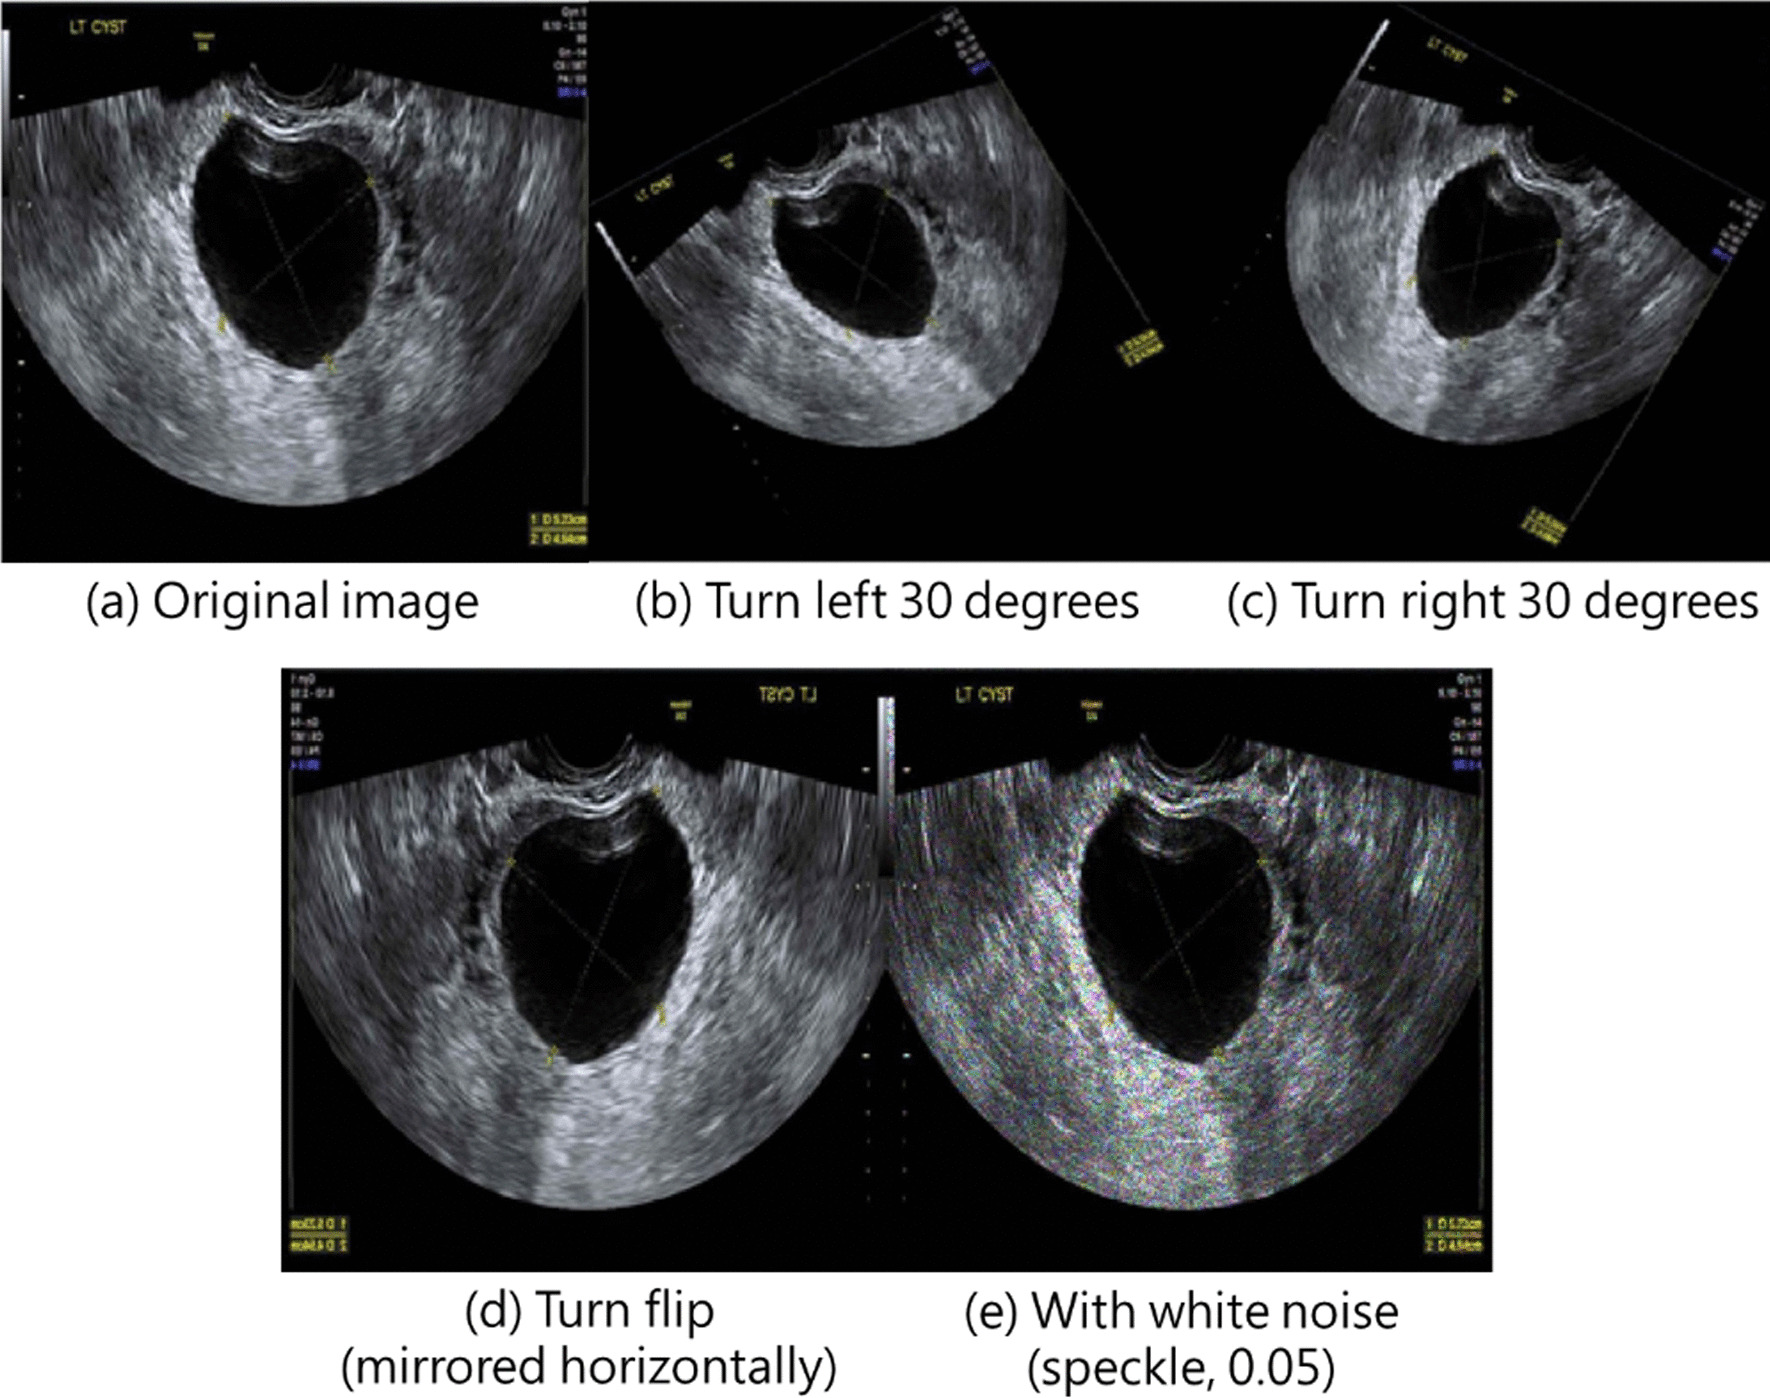

The process from data preprocessing to model training is presented in Fig. 1. Medical record numbers and other relevant information were displayed on the raw images. To comply with IRB protocol, we removed medical record information from the images to ensure data confidentiality and avoid influencing subsequent model training and classification. From both benign and malignant tumor images, 70% were randomly selected and used as training datasets, and the remaining 30% were used as validation datasets. Training dataset images underwent data augmentation, which is a technique often used in machine learning to increase the diversity of training datasets, avoid model overfitting, and improve accuracy. In the present study, data augmentation involved randomized flipping (through which images were mirrored horizontally) and randomized rotation (through which images were rotated by 30° or − 30°). In addition, we add white noise (with speckle noise variance, 0.05) to each image in the training data to generate a number equal to the original training data, so the total number of images in the final training data set are 2654. Figure 2 shows an example of the original image and its data augmentation. Figure 2a–e present the original image, turn left 30 degrees, turn right 30 degrees, turn flip (mirrored horizontally), and with white noise (speckle, 0.05), respectively.

Fig. 2.

An example of the original image and its data augmentation. a–e present the original image, turn left 30 degrees, turn right 30 degrees, turn flip (mirrored horizontally), and with white noise (speckle, 0.05), respectively